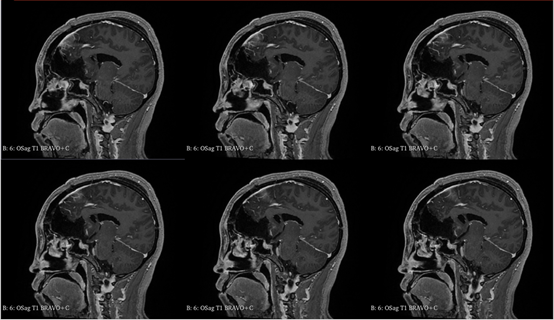

青年女性,因“左眼失明10个月,头痛3个月”就诊我院。

入院诊断:颅内占位病变(前颅窝底)脑膜瘤?;左眼失明;鼻炎

前颅窝底脑膜瘤常起源于前颅底筛骨筛板处的硬膜,瘤体多为双侧生长,少数为偏侧生长,女性稍多于男性。肿瘤可累及鸡冠和蝶骨平台的任何区域,是前颅窝肿瘤中最多见的一种。因为肿瘤位于前颅窝底,额叶在功能上属于“哑区”,患者就诊发现肿瘤时瘤体多已巨大。主要症状可有颅内压增高症状、视力减退、癫痫以及精神症状等。该患者主因“左眼失明10个月,头痛3个月”就诊。术中采用双额冠状开颅,左侧为主,由于肿瘤体积巨大,术中切除少许薄层额叶脑组织,边离断基底、边瘤内减压,分块切除肿瘤,最终探查肿瘤基底主要位于鸡冠、筛板、蝶骨平台、鞍结节、前床突处硬膜,术中见肿瘤供血主要来源于前颅窝底硬膜及大脑前动脉分支,术中仔细辨认供血动脉、过路血管,大脑前动脉及其分支保护完好,术中见视神经、视交叉受压明显,尤其是左侧视神经已缺血苍白,最终达Simpson II级切除。术者体会,该患者术前行多模态重建,可见瘤表数条粗大的静脉,术中切莫过早离断肿瘤的引流静脉,以防因引流不畅致瘤体肿胀出血;术前行多模态重建,利于鉴别供血动脉、过路血管,早期离断供血动脉更利于肿瘤切除;该类肿瘤基底一般较为广泛,不能盲目离断基底,尤其是近鞍结节处,可以于中线处离断基底,进入第一间隙后向两侧探查并保护视神经,待充分缩小瘤体看清楚毗邻的血管神经后再将其完全切除;术毕做好多层颅底重建以防脑脊液漏。另外,该患者术前左眼失明已达10个月,术后第1天即有光感,术后1月复查左眼视力可达50cm内数指,这在临床中非常少见,对于此类病人,不要轻易放弃挽救视力的任何机会。